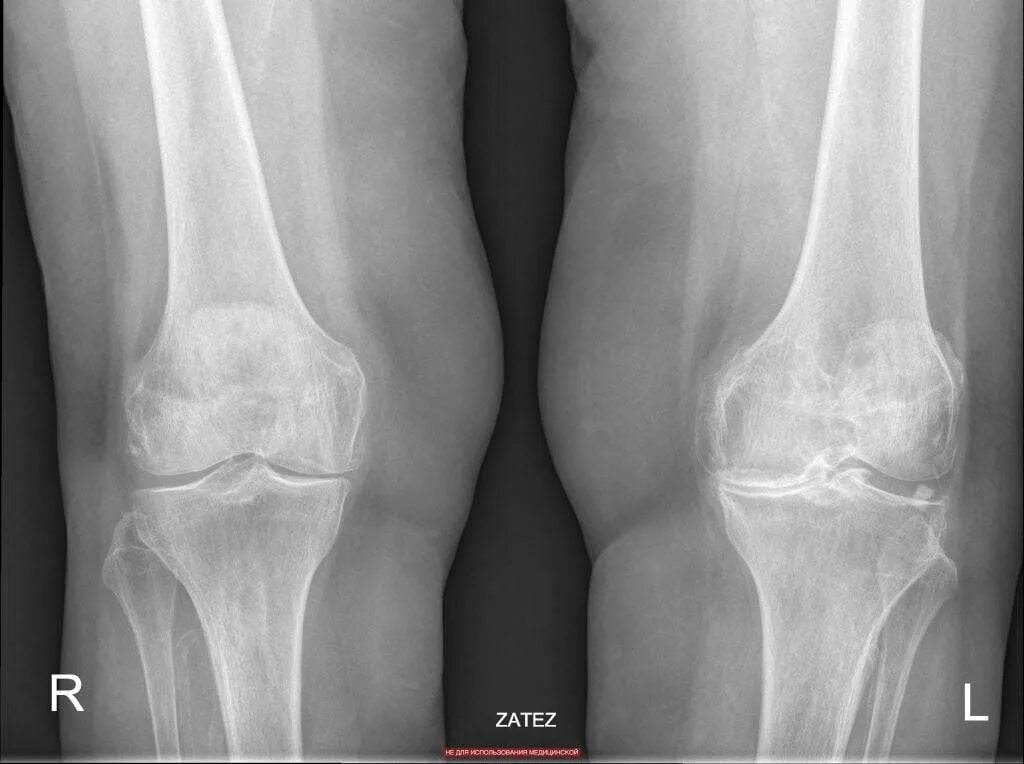

Гонартроз коленного сустава форум